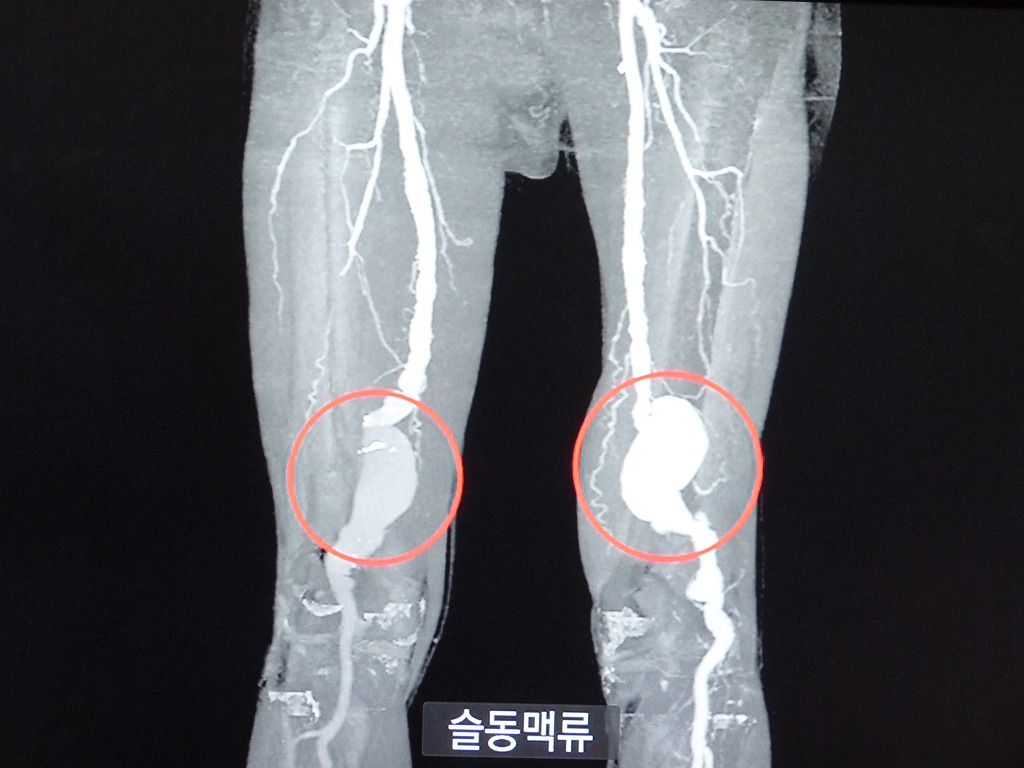

동맥류는 동맥이 있는 곳은 어디든지 발생할 수 있지만 뇌동맥류와 복부동맥류에서 가장 많이 발생한다. 그외에도 신장동맥류, 슬동맥류, 쇄골동맥류 등에서도 발생하고 있다.